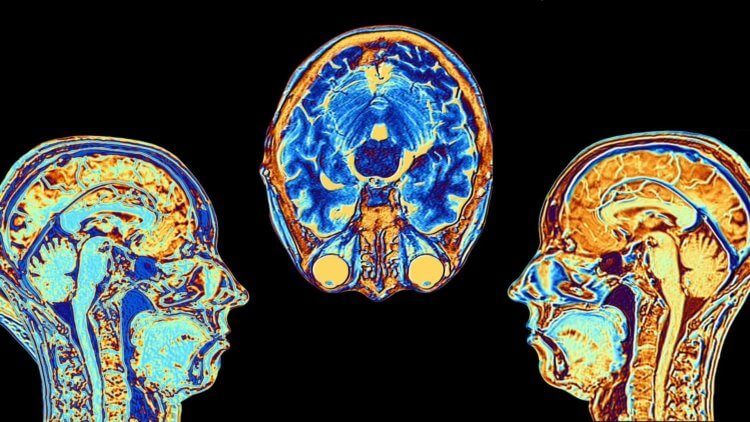

Повреждение определенной области мозга влияет на наши моральные суждения

Изучая общество человекообразных обезьян и их отношения между собой, исследователи все чаще приходят к выводу о том, что истоки морали следует искать в эволюционных изменениях работы мозга. Даже в обществе бонобо раненой особи приходят на помощь сородичи, осматривая и вылизывая раны. Подобное поведение как будто встроено в мозг этих приматов – недавно ученые обнаружили так называемые веретенообразные клетки в мозге бонобо. Эти же клетки задействованные в механизмах самосознания, эмпатии и чувства юмора у человека.

Первоначально эти особенности выявили у людей, но, как это часто бывает, затем обнаружились у бонобо и других приматов. Результаты множества научных исследований показывают, что мозг бонобо имеет физиологическую основу эмпатии. Выходит, мы с вами не такие уж и особенные, а наши моральные суждения можно объяснить размером миндалевидного тела (амигдалы) – области мозга, которая участвует в обработке эмоций и является мозговым “центром страха”.

Нарушение работы миндалевидного тела оказывает влияние на наши суждения о морали

«Исследования на животных показали, что ядро миндалевидного тела играет важную роль в принятии решений и поведении. Мы предполагаем, что именно эта структура ответственна за утилитарные моральные суждения, принимаемые людьми», – пишут авторы научной работы.

Мораль и мозг

Чувство морали неразрывно связано с мозгом, что подтверждает синдром Урбаха-Вите: повреждение амигдалы может привести к трудностям с распознаванием эмоций по лицам, а также бесстрашию перед змеями, пауками, привидениями и фильмами ужасов. На сегодняшний день в мире зарегистрировано всего 400 случаев.Авторы нового исследования предполагают, что повышенная чувствительность к социальной боли может играть определенную роль в неспособности людей с синдромом Урабах-Вите выносить моральные суждения. Пациенты регулярно сообщали, что делать выбор в эксперименте с вагонеткой для них «слишком больно». По-видимому миндалевидное тело имеет решающее значение в механизмах возникновения страха.